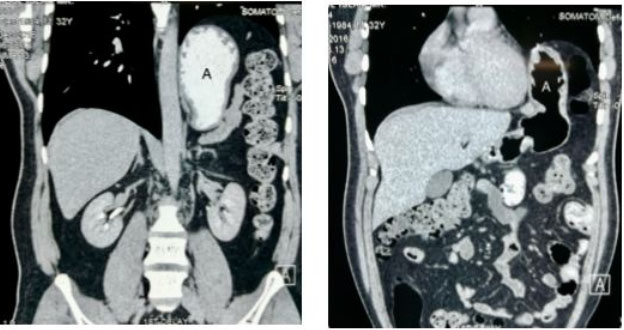

Figure 6: Contrast CT scan, coronal view showing displacement of the stomach (A) in to the left mediastinum.

Figure 7: Contrast CT scan, transverse section showing the stomach (B) located within the chest cavity just beside the heart (A).